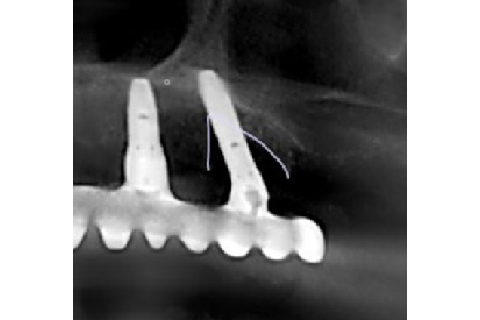

| 患者さま情報 | 81歳 女性 |

|---|---|

| 治療期間 | 2018年10月~112日間 |

| 治療費 | インプラント一本 15,000円(税抜) |

| 治療詳細 | 2014年にインプラント治療を完了。 当医院にて2018年10月にインプラント周囲炎と診断され治療を行う。 ペリソルブとSRP、Er-Yagレーザー照射をフラップ形成下で行った。グラフトレス症例。 |

| 治療におけるリスク・副作用 | ・術後のプラークコントロールが不良の場合、術後感染を起こす可能性があります。 ・ペリソルブの生体に対する安全性は、厚生労働省に認可されています。 |